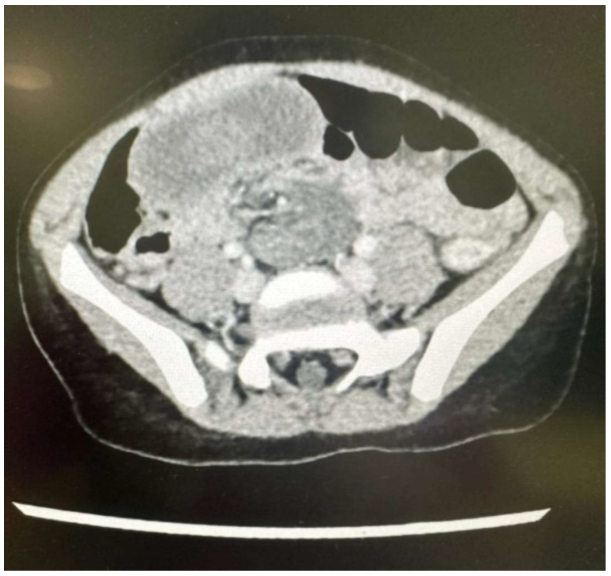

Meckel’s Diverticulum in a 6-Year-Old Girl. A Rare Presentation of Intussusception and Volvulus of Small Bowel

George-Charles Camilleri, Glenn Costa and Mohamed Shoukry. 13(8): 01-04.